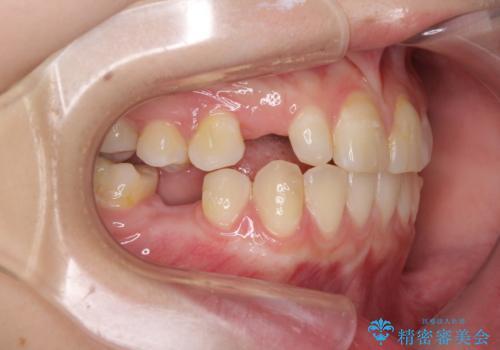

欠損と残存乳歯 矯正治療とインプラント治療

- 残存した乳歯や歯の欠損、歯並びを気にして来院された患者様です。

乳歯を残した状態は予後がよくないこと、矯正治療と補綴治療を総合的に進めていきたいとのことで、インビザラインによる矯正治療とインプラント補綴治療を並行して進めていくこととしました。